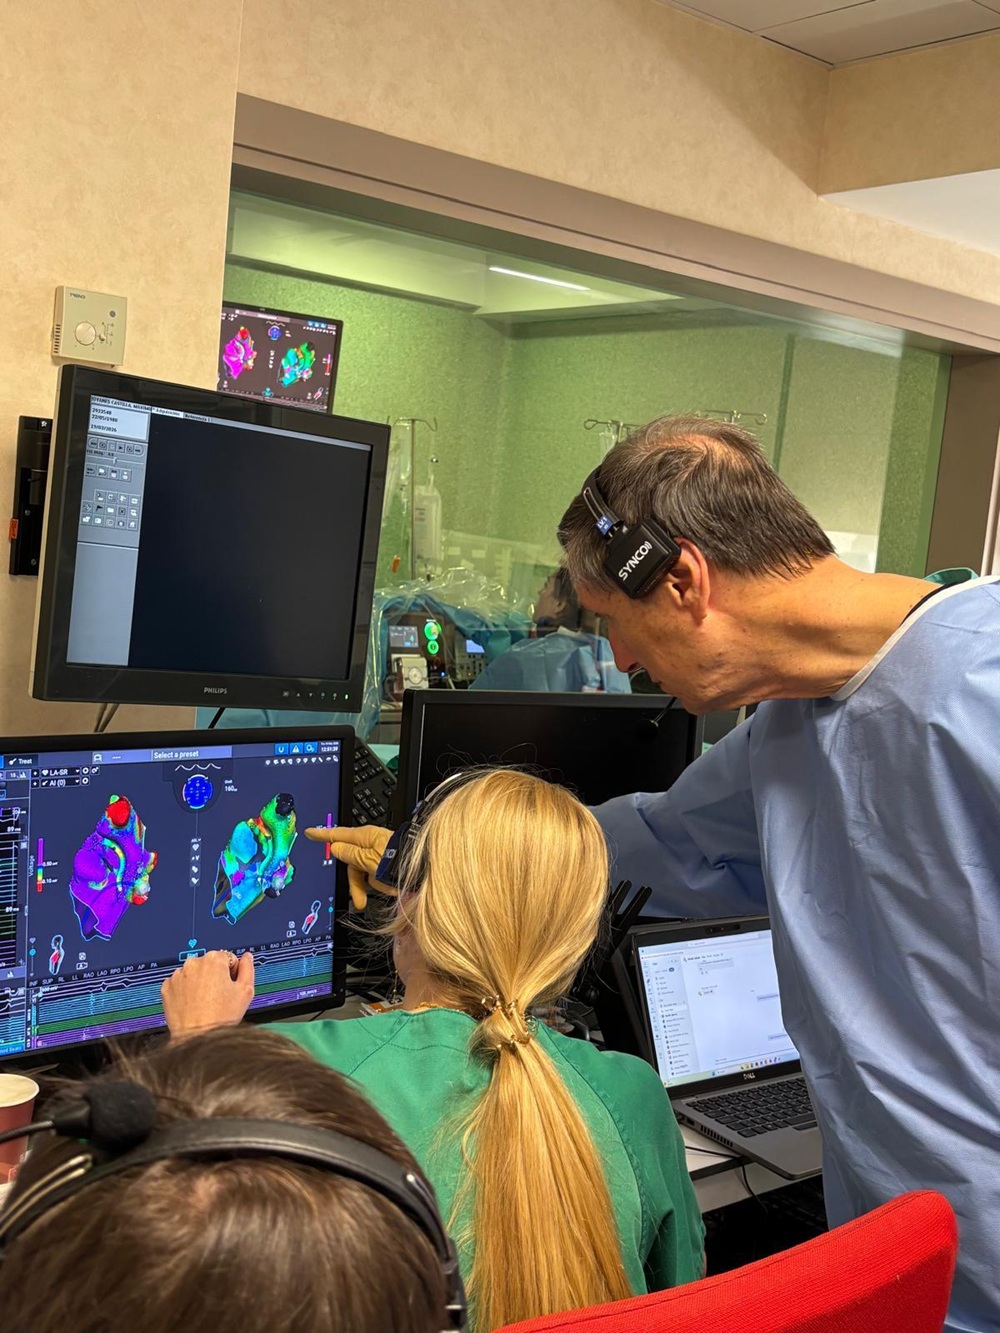

HM Hospitales recibe a 90 alumnos en prácticas y refuerza su compromiso con la formación sanitaria en Málaga

HM Hospitales ha dado la bienvenida a un nuevo grupo de alumnos del Grado Superior en Imagen para el Diagnóstico, de Lab…